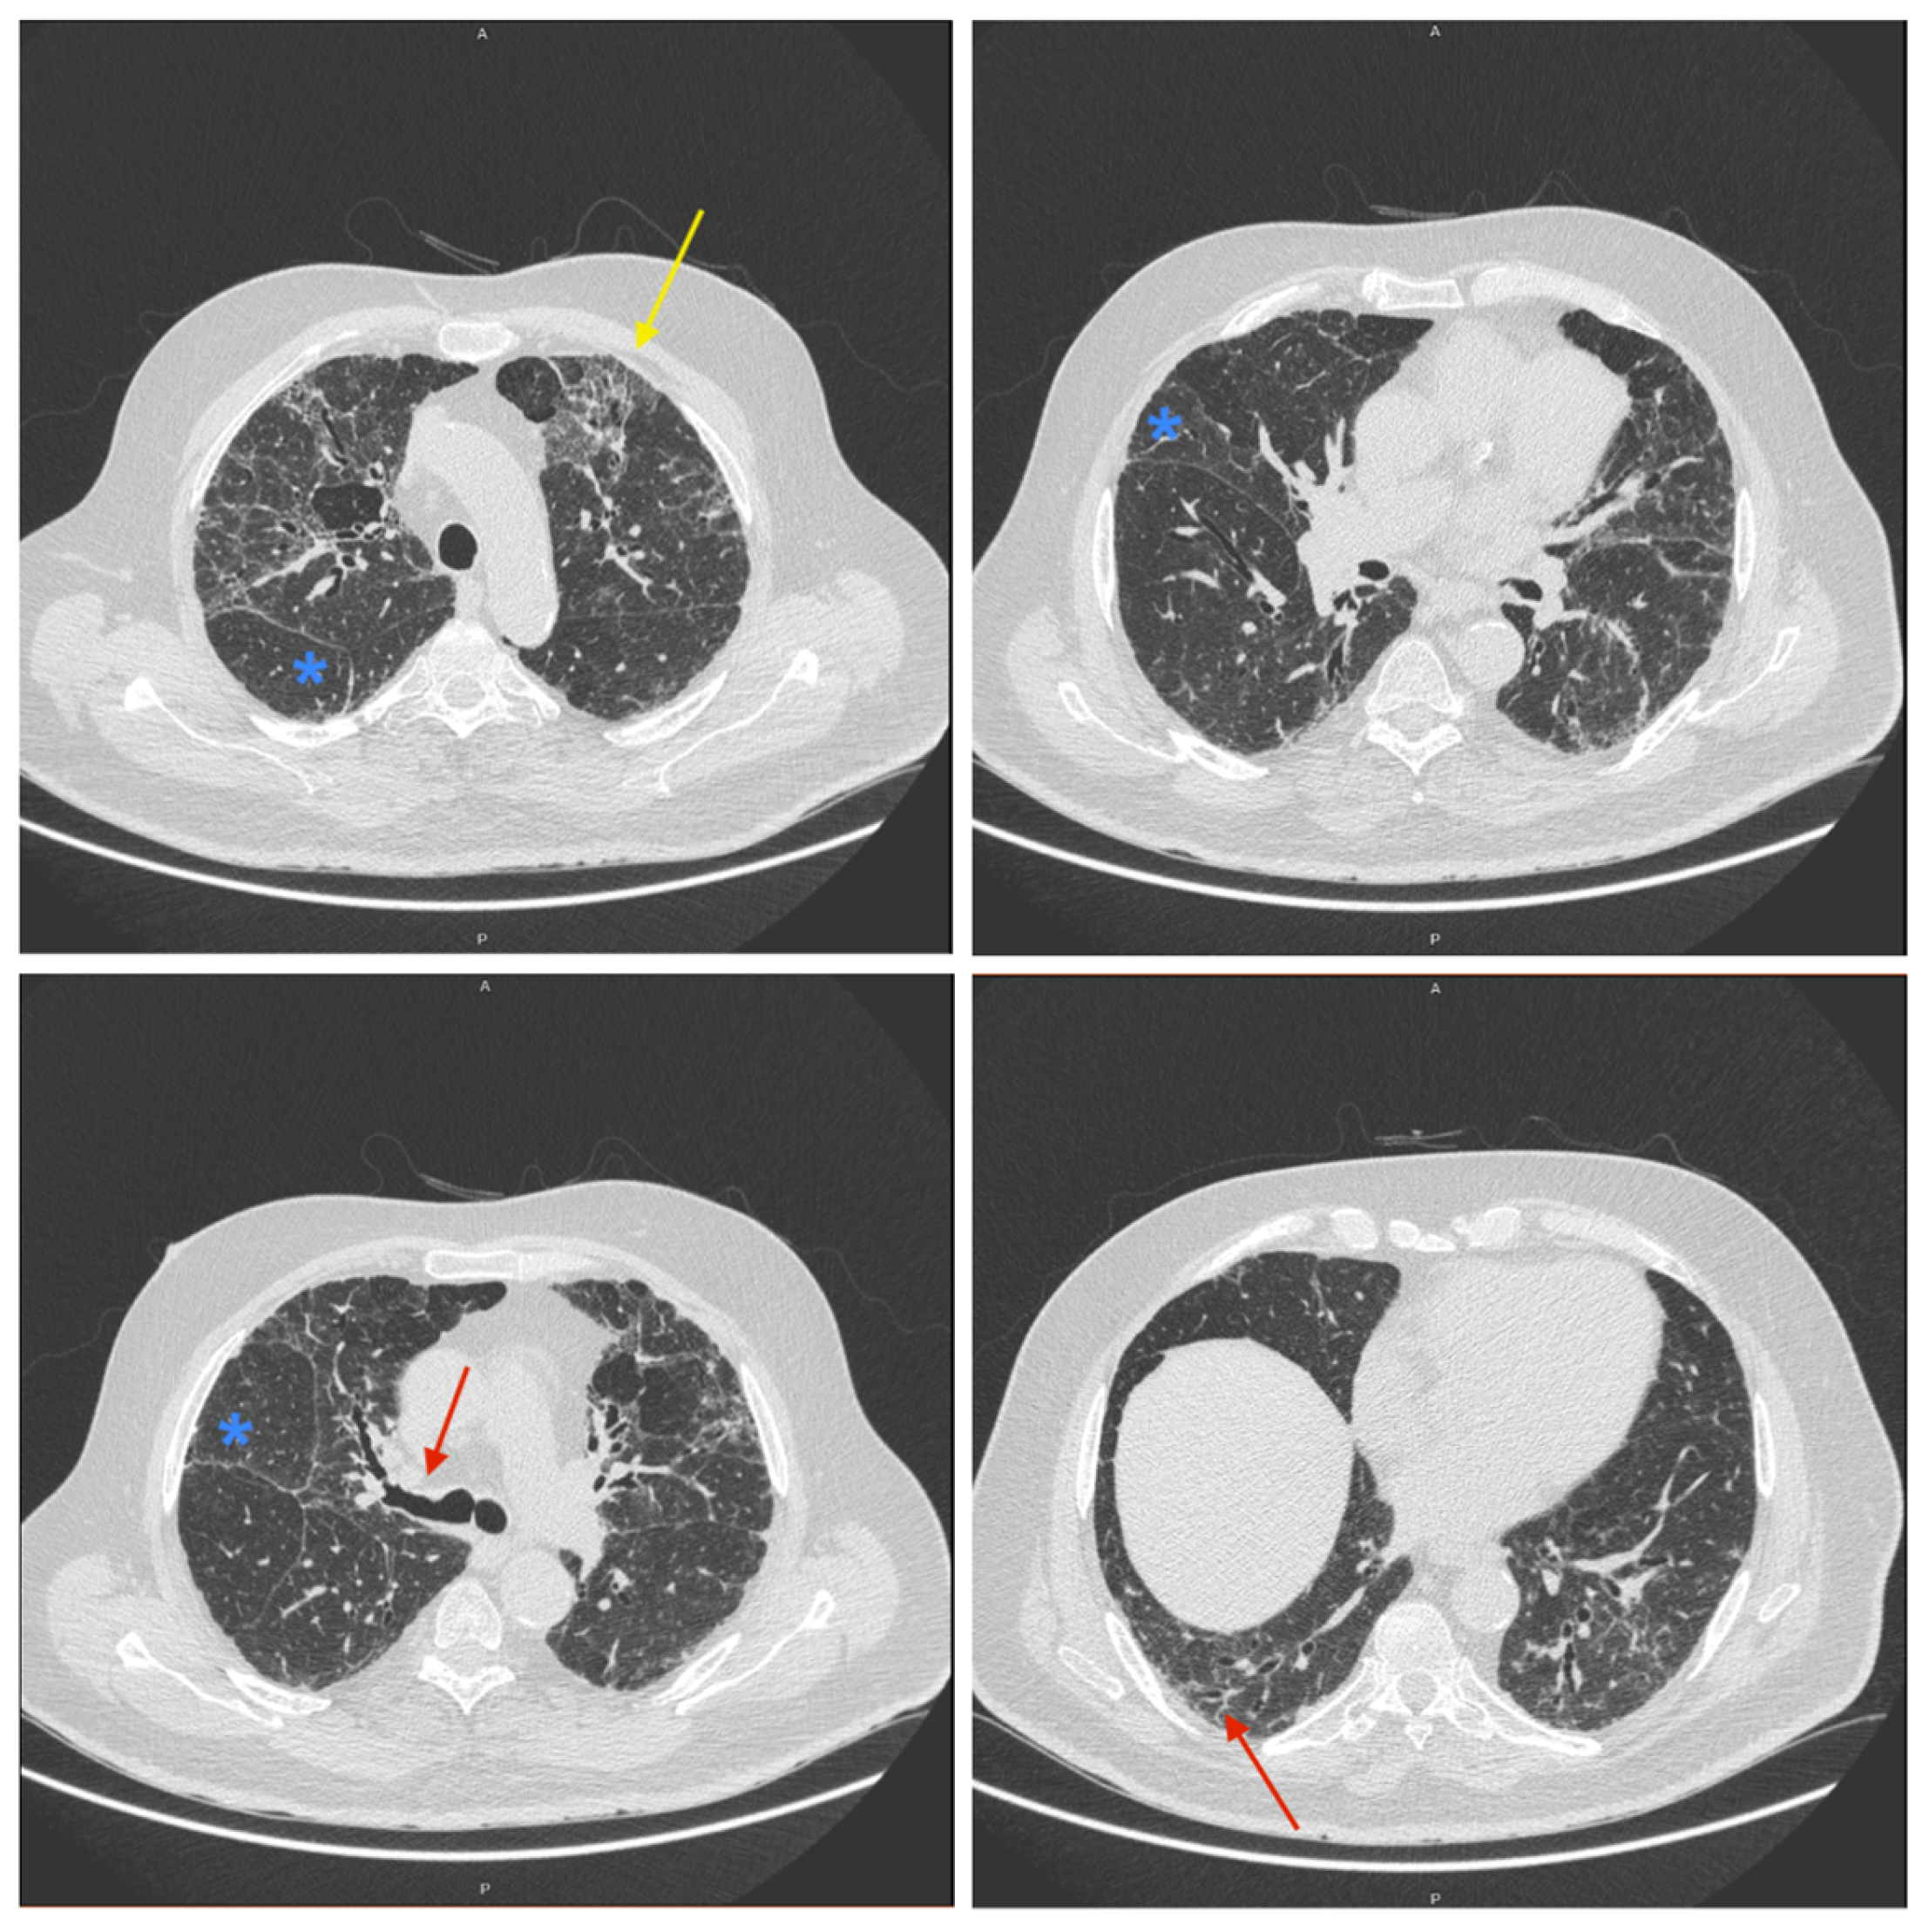

2. Detailed Case Description